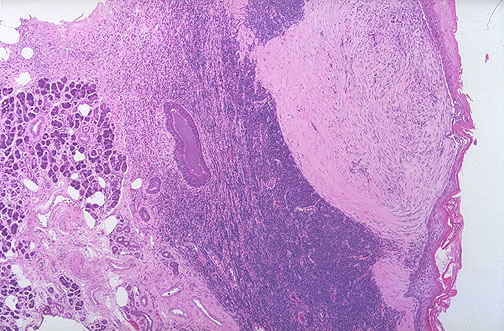

Here is a benign lymphoepithelial cyst of salivary gland. These are typically unilateral and unilocular cysts involving the parotid gland. The cyst is well-demarcated from surrounding salivary gland.